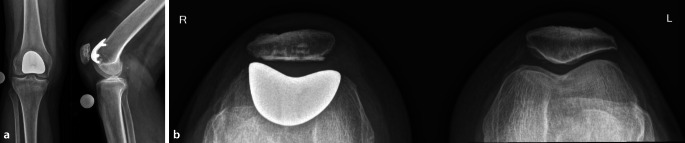

Background: Isolated patellofemoral osteoarthritis is a degenerative disease of the knee joint that may cause disabling pain and functional limitations. When conservative therapy has failed, arthroplasty can significantly improve the quality of life and mobility of affected patients. In such cases, it is important to select the most suitable implant for the patient on an individual basis. This article discusses the decision-making process between patellofemoral arthroplasty, total knee replacement, and bicondylar replacement without patellar resurfacing.

Therapeutic options: Patellofemoral arthroplasty is mainly used in younger patients and, if implanted correctly, can lead to good results and a delay in the need for total knee replacement. In older patients with isolated patellofemoral osteoarthritis, total knee replacement is usually the preferred option due to its predictable good outcomes and a lower revision rate. In selected cases, particularly with severely thinned patella, retropatellar resurfacing should not be done.